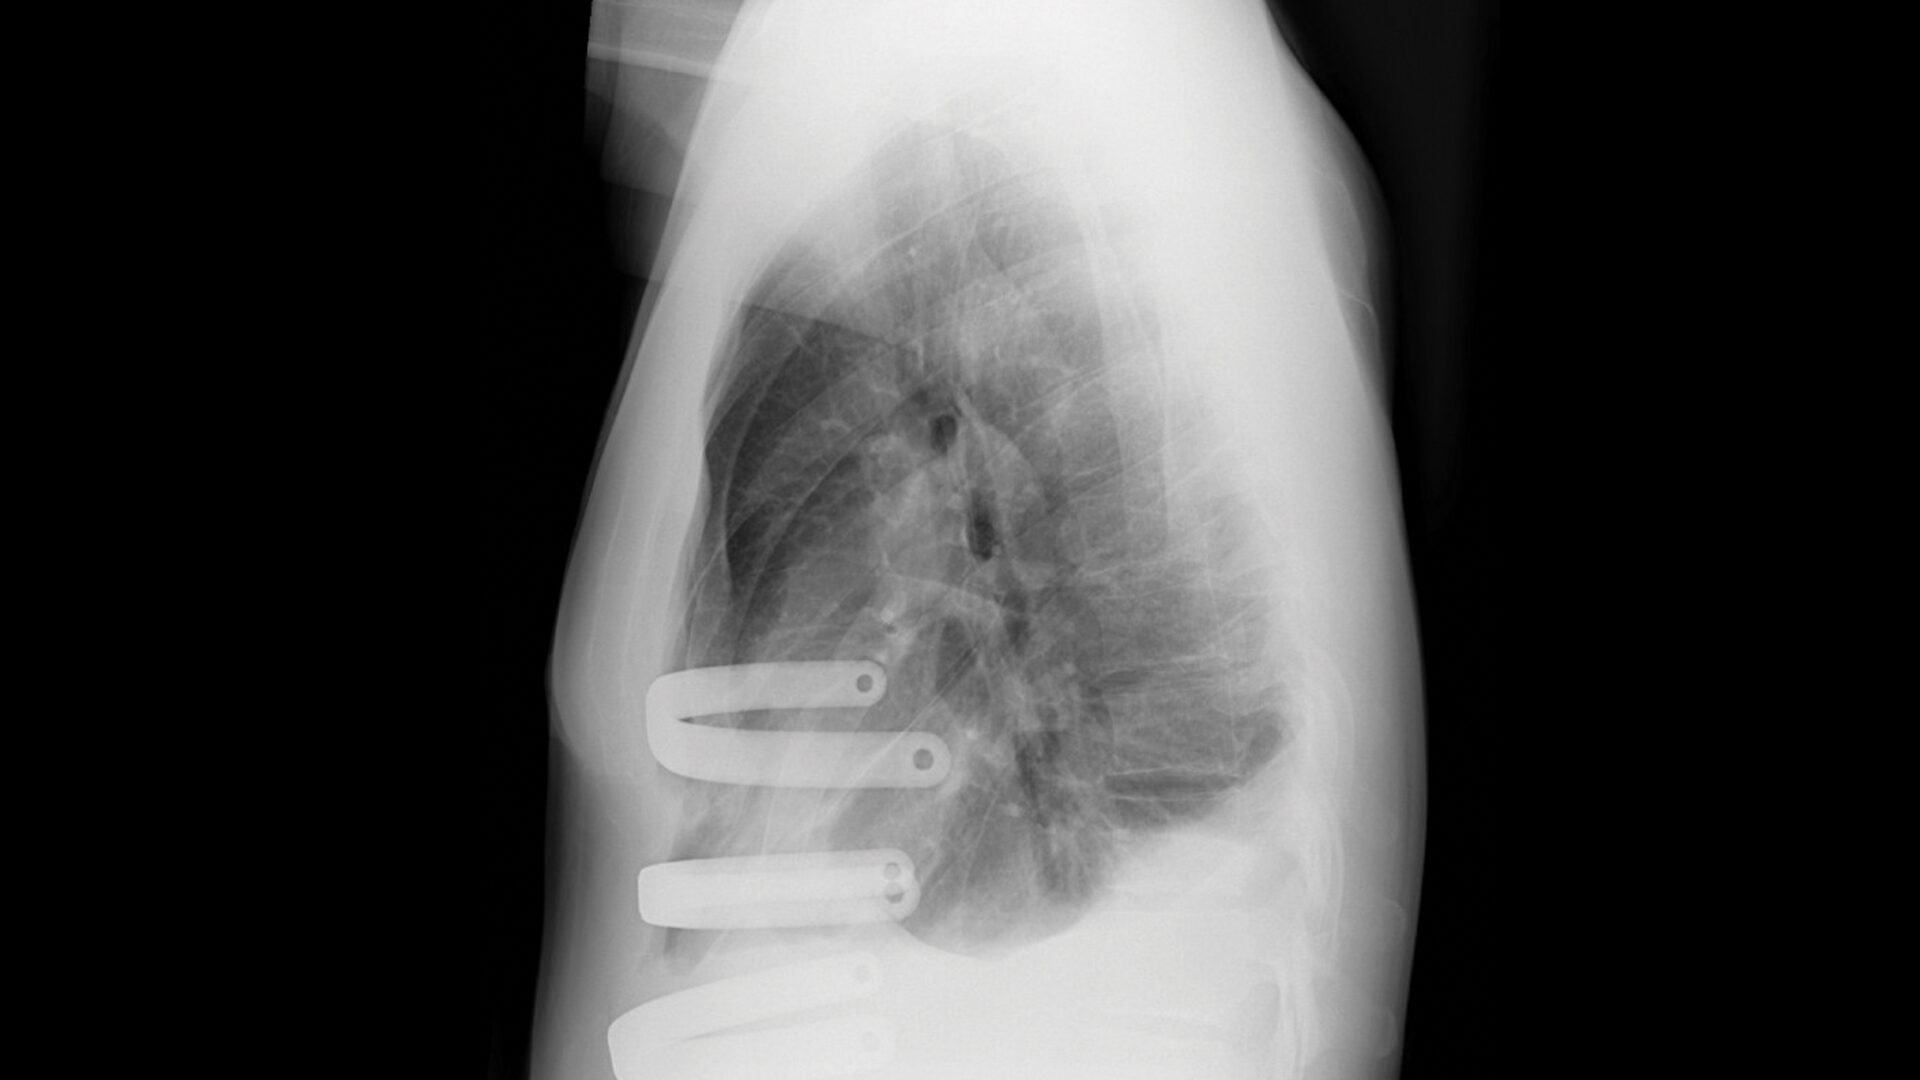

Postoperative X-ray showing placement of the three U-shaped titanium bars. Source: NYU Langone Health

Under thoracoscopic guidance, Dr. Bizekis performed the Nuss procedure via two bilateral, 3-centimeter lateral chest wall incisions. After freeing up tissue under the sternum with a handheld sound incision device, he inserted three U-shaped, malleable titanium bars using passers connected to a guiding rod, conforming the bars to the chest wall.

“We decide intraoperatively how many bars to use. Although one or two bars is common, we implanted three bars because of the severity of this case,” Dr. Bizekis says.

During the operation, the bars were positioned one interspace apart in a submuscular plane along the outer surface of the pectoralis muscle and inverted to remodel the anterior chest wall, achieving correction without tissue resection, dissection, or chest tube drainage. The bars were secured to the lateral chest wall with FiberWire sutures.